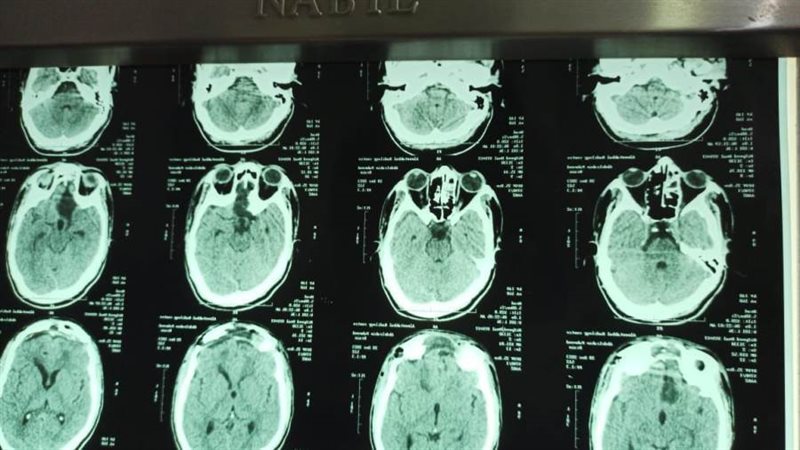

نجح فريق طبي بقسم جراحة المخ والأعصاب، بالتعاون مع قسم التخدير بمستشفي سوهاج الجامعي في استئصال اكبر الأورام من حيث الحجم بقاع الجمجمة، يبلغ ١٣٢ سنتمتر مربع، لشاب يبلغ من العمر ٢٢ سنة وإنقاذه من فقد كلي للبصر، صرح بذلك الدكتور حسان النعماني رئيس الجامعة.

وقال النعماني إن الفريق الطبي بالمستشفى قام بإجراء التدخل الجراحي الدقيق لإنقاذ حياة الشاب، وذلك بعد معاناة استمرت٣ سنوات متصلة كان يعاني من تدهور فى البصر مع صداع مزمن واختلال فى التصرفات، حيث تم استئصال "الورم" بنجاح.

من جانبه قال الدكتور مجدي القاضي عميد كلية الطب البشري ورئيس مجلس إدارة المستشفيات الجامعية، أنه عند وصول الشاب إلى المستشفى كان يعاني من ضعف شديد بالنظر وارتشاح بالعصب البصرى، وصل الي مرحلة ما قبل فقدان البصر، فتم اجراء عملية استئصال كلى للورم وخروج المريض فى حالة وعى كامل مع عودة البصر.